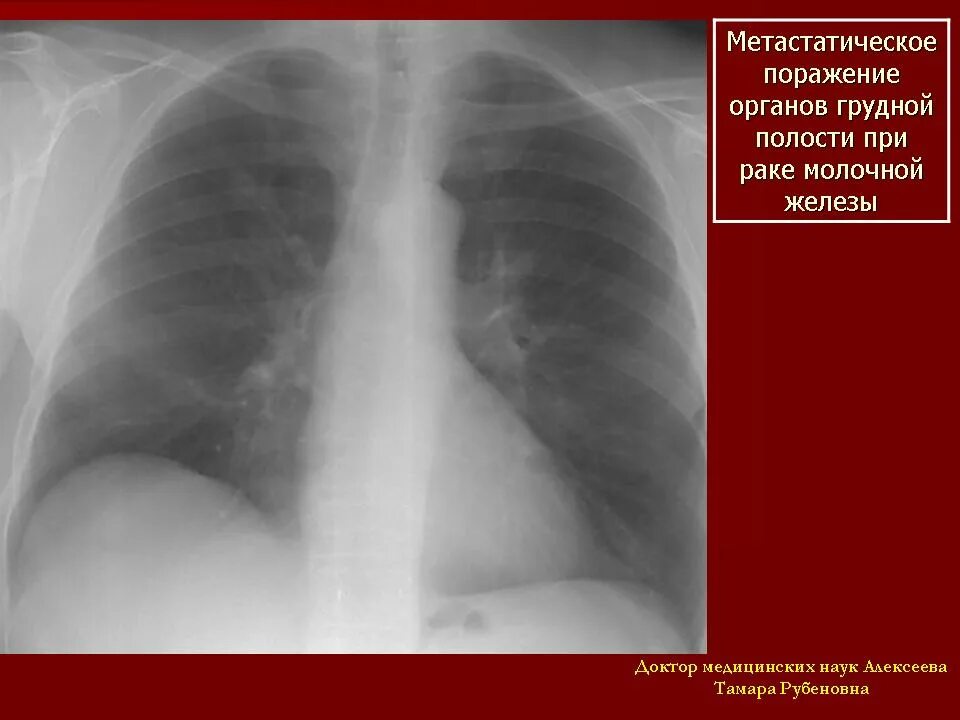

Рмж метастазы в легкие